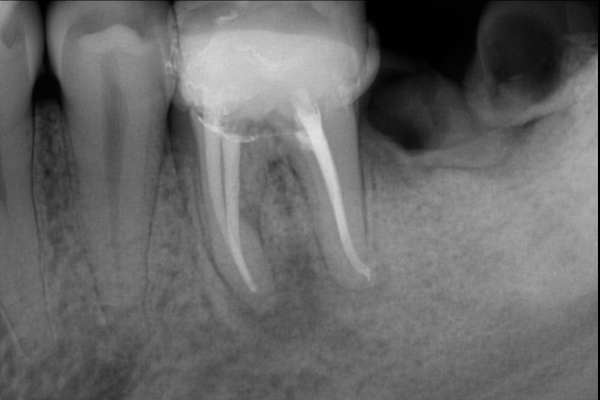

Endodoncia por caries en la raíz de la pieza dental

Paciente X de B años de edad, llega con amplia caries en la zona de a raíz. Se realiza endodoncia para salvarlo de una extracción. Al final se rehabilitó su pieza dental con una incrustación.

El paciente feliz, al finalizar su tratamiento